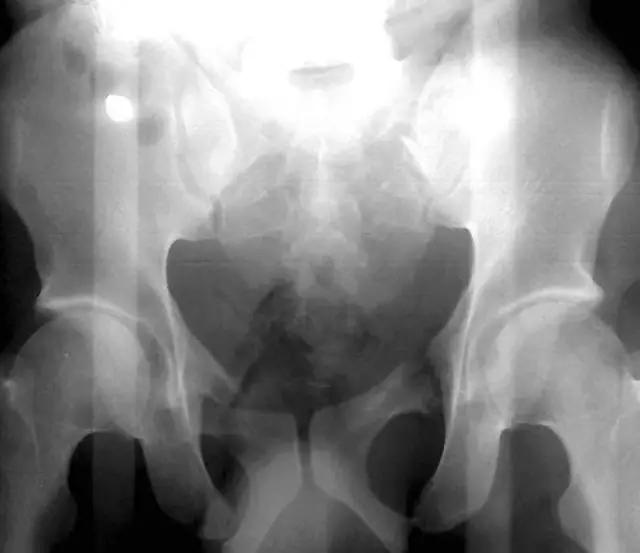

2. Malgaigne 骨折 (bucket handle 骨折,即桶柄骨折)

不稳定性骨盆骨折伴有前方和后方的骨折线累及髋关节。

(来源:radiopaedia)

3. Straddle 骨折

双侧耻骨上下支骨折。

(来源:learning radiology)